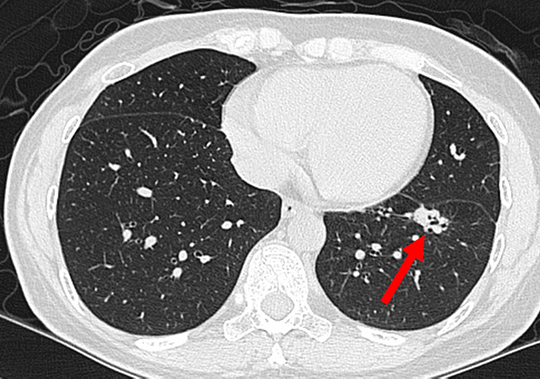

53歲女性健康檢查,肺部低劑量電腦斷層(LDCT)發現2公分高度可疑肺癌的結節(4B/(4X)(箭號))。手術後証實罹患肺腺癌。